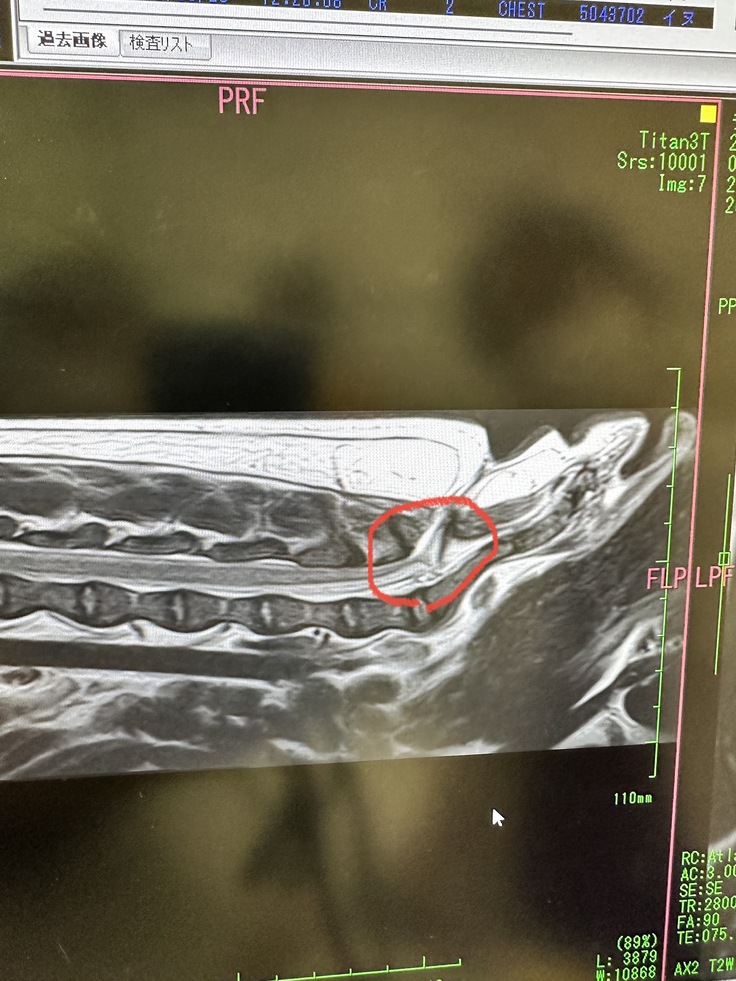

CTやMRIによる詳しい検査により

腰骨辺りの髄膜を包む膜が引っ張られ袋状になっている箇所がある事から麻痺や神経障害があり

排尿や排便に障害を起こしている為、改善する手術を行う。

腰骨も陥没が見受けられ陥没した所から神経の膜を引っ張っているような状態だそうです。

下の写真の赤い○の中にある三角の物は本来無いもので、引っ張られた膜が映ったものです。